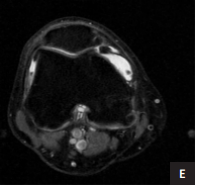

METHODS: This study recruited young and middle-aged participants (18-45 years), including both cervical instability patients and healthy controls, through the Spine Department Outpatient Clinic of Wangjing Hospital, China Academy of Chinese Medical Sciences, as well as community-based recruitment. All participants underwent cervical magnetic resonance imaging examinations. On the axial magnetic resonance imaging images, five key anatomical structures were manually annotated: intervertebral disc, facet, prevertebral muscle, deep muscle group in the back of the neck, and superficial muscle group in the back of the neck. A deep learning algorithm was then employed to develop a predictive model for cervical instability, utilizing both the original images and the delineated regions of interest. Finally, the model's predictive performance was systematically evaluated and validated.